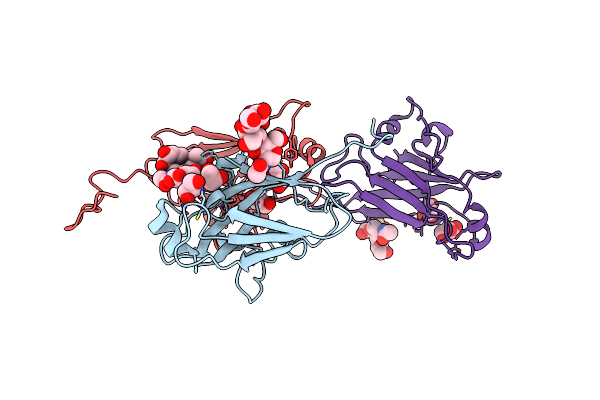

Crystal Structure Of Spike Protein Receptor Binding Domain Of Escape Mutant Sars-Cov-2 From Immunocompromised Patient (D146*) In Complex With Human Receptor Ace2

Organism: Homo sapiens, Severe acute respiratory syndrome coronavirus 2

Method: X-RAY DIFFRACTION Resolution:3.08 Å Release Date: 2021-12-08 Classification: VIRAL PROTEIN Ligands: ZN, CL, NAG |